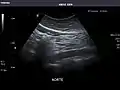

Aorta